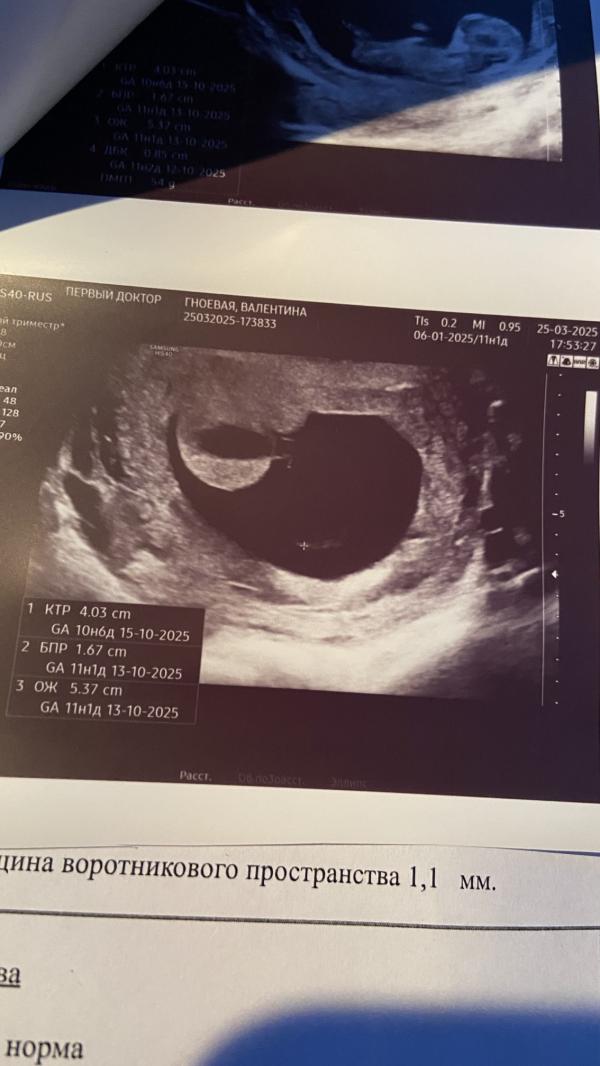

Сходили с мужем на узи. На скрининг назначили прийти 31.03. На фото- какое-то непонятное образование. И прикол в том, что врач не смог объяснить что это!! (Платная клиника). И меня это очень пугает!! Вдруг у кого было подобное на узи, скажите, что это 🙄 сказали на скрининге должно хорошо видно что это, там скажут скорее ну или обратитесь в дальнейшем в центр медицины плода. 👍🏻👍🏻👍🏻👍🏻

Да. Есть другие фото, там ребеночек и прям над ним вот эта сиська